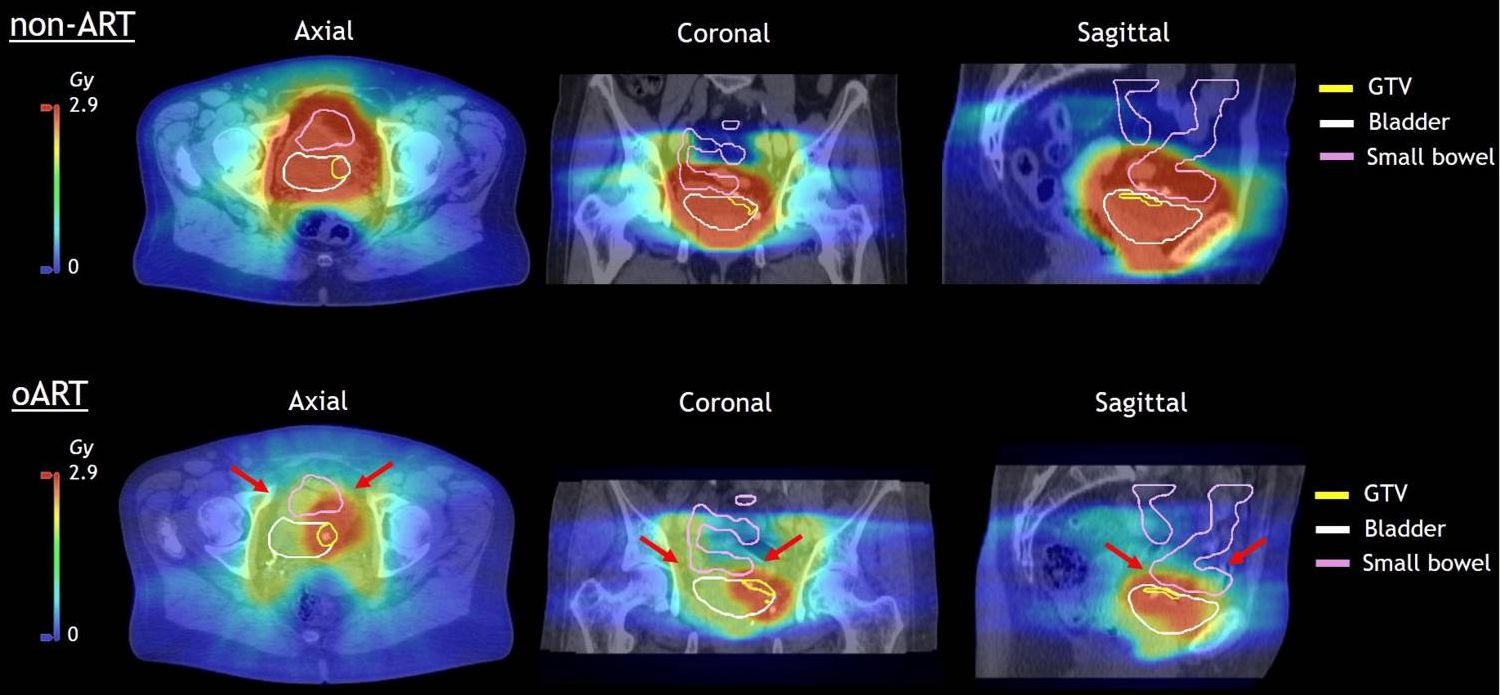

The third place case report, submitted by Amsterdam UMC, explored the potential of daily oART for bladder cancer to limit high-dose exposure of healthy tissue, compared to conventional non-adaptive radiotherapy. The paper examines a bladder cancer patient treated after cystoscopic tumor resection to 40 Gy in 20 sessions, with a simultaneous boost of 15 Gy to the tumor bed. By utilizing daily online adaptation of the treatment plan, the team was able to achieve smaller planning target volume margins. This reduced the dose to normal healthy tissues in the bladder and bowel, while maintaining 100% coverage of the target region.

Non-adaptive vs adaptive dose to the small bowel

The figure shows the difference in dose to the small bowel in the worst non-adaptive radiotherapy case (upper panels, contours depicted in pink) compared to the online adaptive radiotherapy treatment plan (lower panels). (From Figure 6, Azzarouli et al.)